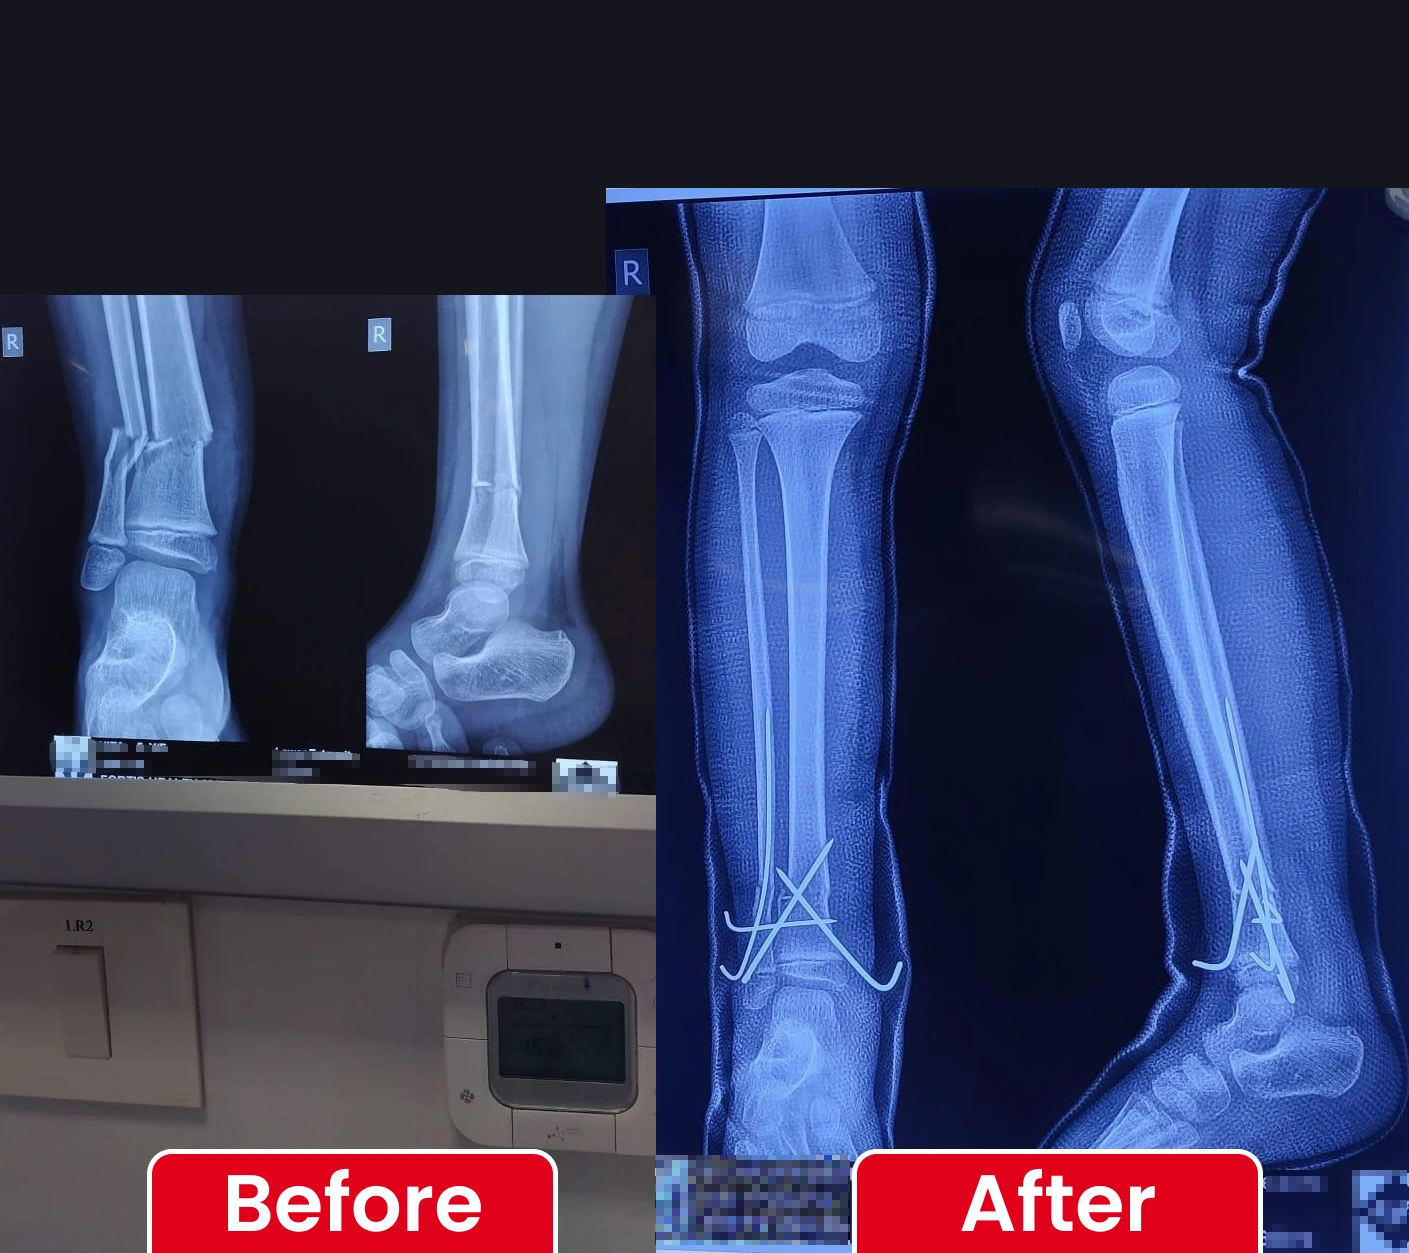

Expert care for complex fractures and injuries to ensure rapid recovery and restored function.

Successful Fracture & Trauma Surgeries